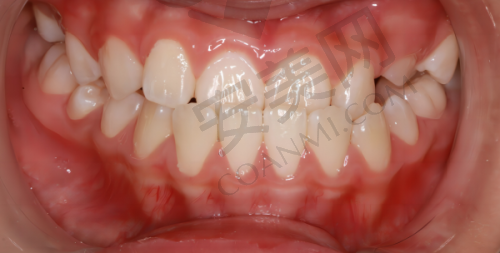

我第一次来到深圳铭德口腔,前台的工作人员非常热情地接待了我,引导我填写了相关的信息表格,包括个人基本信息、牙齿状况以及既往病史等。填完表格后,护士带我去拍了牙齿的X光片和口腔的全景照片,这些检查可以帮助医生全方面了解我的牙齿和颌骨的情况。之后,我见到了为我进行矫正的医生,医生非常耐心地查看了我的检查结果,和我沟通了我的牙齿问题,比如牙齿拥挤、咬合不正等,还详细地给我介绍了几种适合我的矫正方案,包括传统金属牙套、陶瓷牙套和隐形牙套,并分析了每种方案的优缺点和价格。在医生的专精建议下,我结合自己的需求和经济情况,选择了隐形牙套矫正方案。

随着时间的推移,我明显感觉到了牙齿的变化。在佩戴隐形牙套几个月后,牙齿的拥挤情况得到了改善,排列逐渐变得整齐。咬合也比以前好了特别多,吃东西的时候更加轻松。而且,因为牙齿变整齐了,我的笑容也变得更加自信了,不再像以前那样不敢笑。在整个矫正过程中,深圳铭德口腔的医生和护士都非常负责,每次复诊的时候,医生都会仔细检查我的牙齿情况,根据牙齿的移动进度为我更换新的牙套。护士也会耐心地提醒我佩戴牙套的注意事项,让我感受到了他们的专精和贴心。